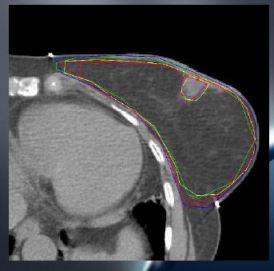

Kontúrovanie boostu CTV-PTV, literatura

CTV by malo byť definované na základe:

- Predoperačného klinického vyšetrenia

- Predoperačných zobrazovacích metód (NMG, USG)

- Zmeny viditeľné na CT: jazva, seróm, klipy

Definícia boost CTV

Veľkosť CTV a PTV lemov

- CTV Lemy

- Holland et al: >2cm

- Vinci et al 2004: 1cm

- Young boost trial: 1,5cm

- PTV lemy:

- Literatura: variácie od 0,5-1cm

- Young boost trial: 0,5cm

Doporučenia pre delineáciu CTV a PTV boostu

- CTV boost:

- Tkanivo prsníka okolo tumoru (před lumpektómiou) + lem 1,5cm

- Zabrať do objemu klipy a vnútornú jazvu!!!

- Alebo: kavita po excízii (seróm) + 1,5cm

- PTV boost:

- CTV + 0,5cm vo vrtkých smeroch (rátať s nepresnosˇami nastavenia, pohybom orgánov)

- V prípade elektrónového poľa nie je definovaný lem zo strany vstupu poľa